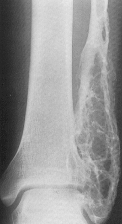

SARCOMUL EWING

Se localizeaza la nivelul oaselor lungi, cu predilectie în portiunea medie a diafizei.

Aspectul radiologic în stadiul incipient nu este caracteristic. Apar zone de osteoliza în compacta diafizara a oaselor lungi cu diametrul în jur de 1 cm. Ulterior diafiza se îngroasa fuziform, tumora se extinde, distruge corticala apoi dezlipeste periostul producâd periostoza sub forma unor lame suprapuse. Prima lama osoasa din apropierea corticalei este strapunsa de tumora formându-se o a doua lama de periostoza si asa mai departe astfel ca osul apare înconjurat de lamele osoase suprapuse asemanatoare foilor de ceapa

În stadiul avansat, corticala este partial distrusa, osul este deformat, cu contururi fluu; tumora invadeaza partile moi, se pot produce fracturi.